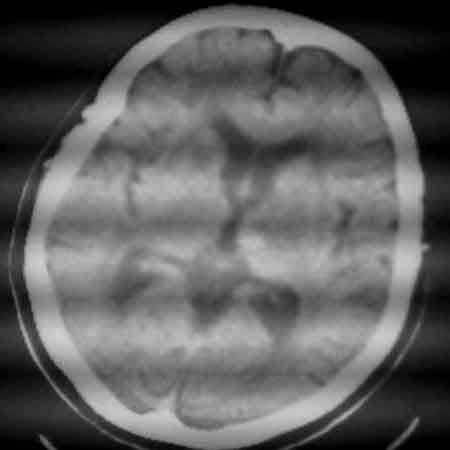

标题: CT8860:陈旧性脑出血 [打印本页]

标题: CT8860:陈旧性脑出血

女81岁,头晕、流延。